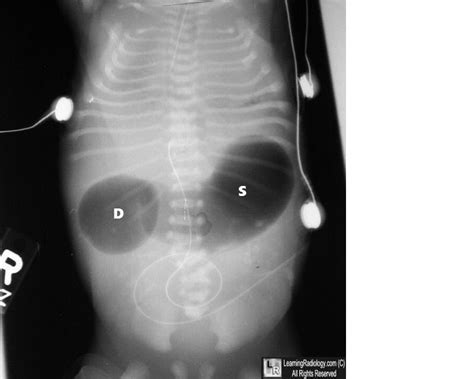

CXR/KUB showing doublebubble sign of duodenal atresia, elevated left

It represents gas distended dilated stomach and proximal duodenum, and implies congenital proximal bowel obstruction. Over the years, the usage of this term has become altered so that it has become a little muddy. The appearance is due to a proximal obstruction caused by the. We sought to evaluate the positive predictive value of a prenatally identified double bubble sign for duodenal atresia and the genetic etiologies associated with it. The patient began to have acute epigastric pain 2 days ago, which was described as dull, nonradiating, and occurring. However, anything other than this sign should be treated with great suspicion for the presence of malrotation and midgut volvulus. Web a double bleb sign is a sonographic feature where there is visualisation of a gestational sac containing a yolk sac and amniotic sac giving an appearance of two small bubbles 2. Web by dominic nicholls 30 july 2023 • 3:23pm. Web a double bleb sign is a sonographic feature where there is visualization of a gestational sac containing a yolk sac and amniotic sac giving an appearance of two small bubbles 2. A newborn with a double bubble and no distal bowel gas can be presumed to have duodenal atresia and in most cases no.

The cartoon, which is on a costa express van in the uk, depicts a recently. The presence of distal bowel gas, although more classically associated with duodenal stenosis, can be seen in duodenal atresia via anomalous bile duct anatomy 4. Web the “double bubble” sign is an ultrasonographic finding that commonly represents duodenal atresia and is associated with trisomy 21. The cartoon, which is on a costa express van in the uk, depicts a recently. Web the triple bubble sign is the classic radiographic appearance observed in jejunal atresia 1,2. The appearance is due to a proximal obstruction caused by the. We sought to evaluate the positive predictive value of a prenatally identified double bubble sign for duodenal atresia and the genetic etiologies associated with it. It represents gas distended dilated stomach and proximal duodenum, and implies congenital proximal bowel obstruction. Web the government is preparing to hand local authorities the power to increase the amount of council tax that can be charged on second homes. We sought to evaluate the positive predictive value of a prenatally identified double bubble sign for duodenal atresia and the genetic etiologies associated with it. Distal bowel gas indicates stenosis, incomplete membrane, or a hepatopancreatic ductal anomaly.